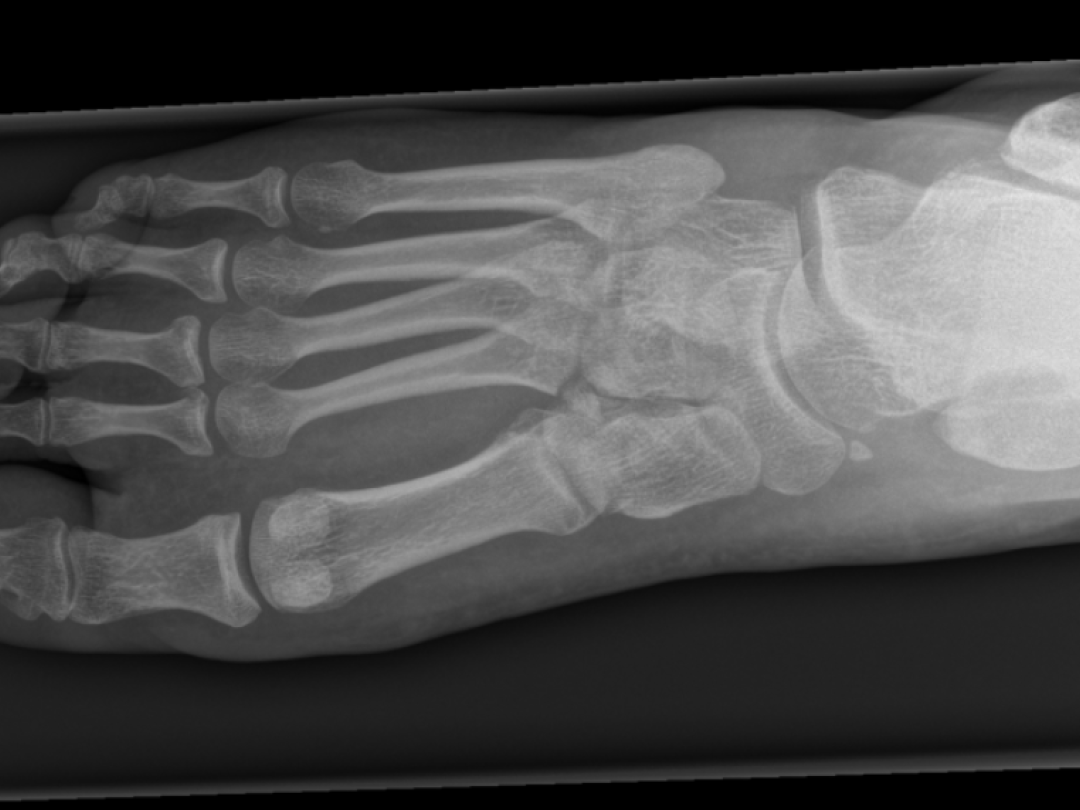

Mis het Lisfranc-letsel niet

Röntgen van voet

Het Lisfranc-letsel is relatief zeldzaam en gaat vaak gepaard met subtiele klinische en radiologische afwijkingen. Hierdoor wordt 20-50% van deze letsels aanvankelijk gemist. Een gemiste diagnose verhoogt het risico op posttraumatische artrose.

Wij zagen een 51-jarige man op de polikliniek Heelkunde met een plantair hematoom en het onvermogen om de rechter voet te belasten. Drie weken eerder was hij gestruikeld. Toen hij daarna bij de huisartsenpost kwam, was de werkdiagnose ‘contusie, dan wel bandletsel van de voet of enkel’. Nadat wij een aanvullende CT-scan van de voet hadden verricht, stelden wij de diagnose ‘Lisfranc-letsel’. We duidden het letsel als stabiel en behandelden de patiënt conservatief. Twaalf weken na het trauma ervoer de patiënt nog altijd pijnklachten en was hij ontevreden over het beloop.

Het is belangrijk de diagnose ‘Lisfranc-letsel’ tijdig te stellen, zodat adequate therapie direct kan worden ingezet. Dat geeft de gunstigste prognose. Bij een patiënt met het onvermogen de voet te belasten en een plantair hematoom moet altijd aan een Lisfranc-letsel worden gedacht.